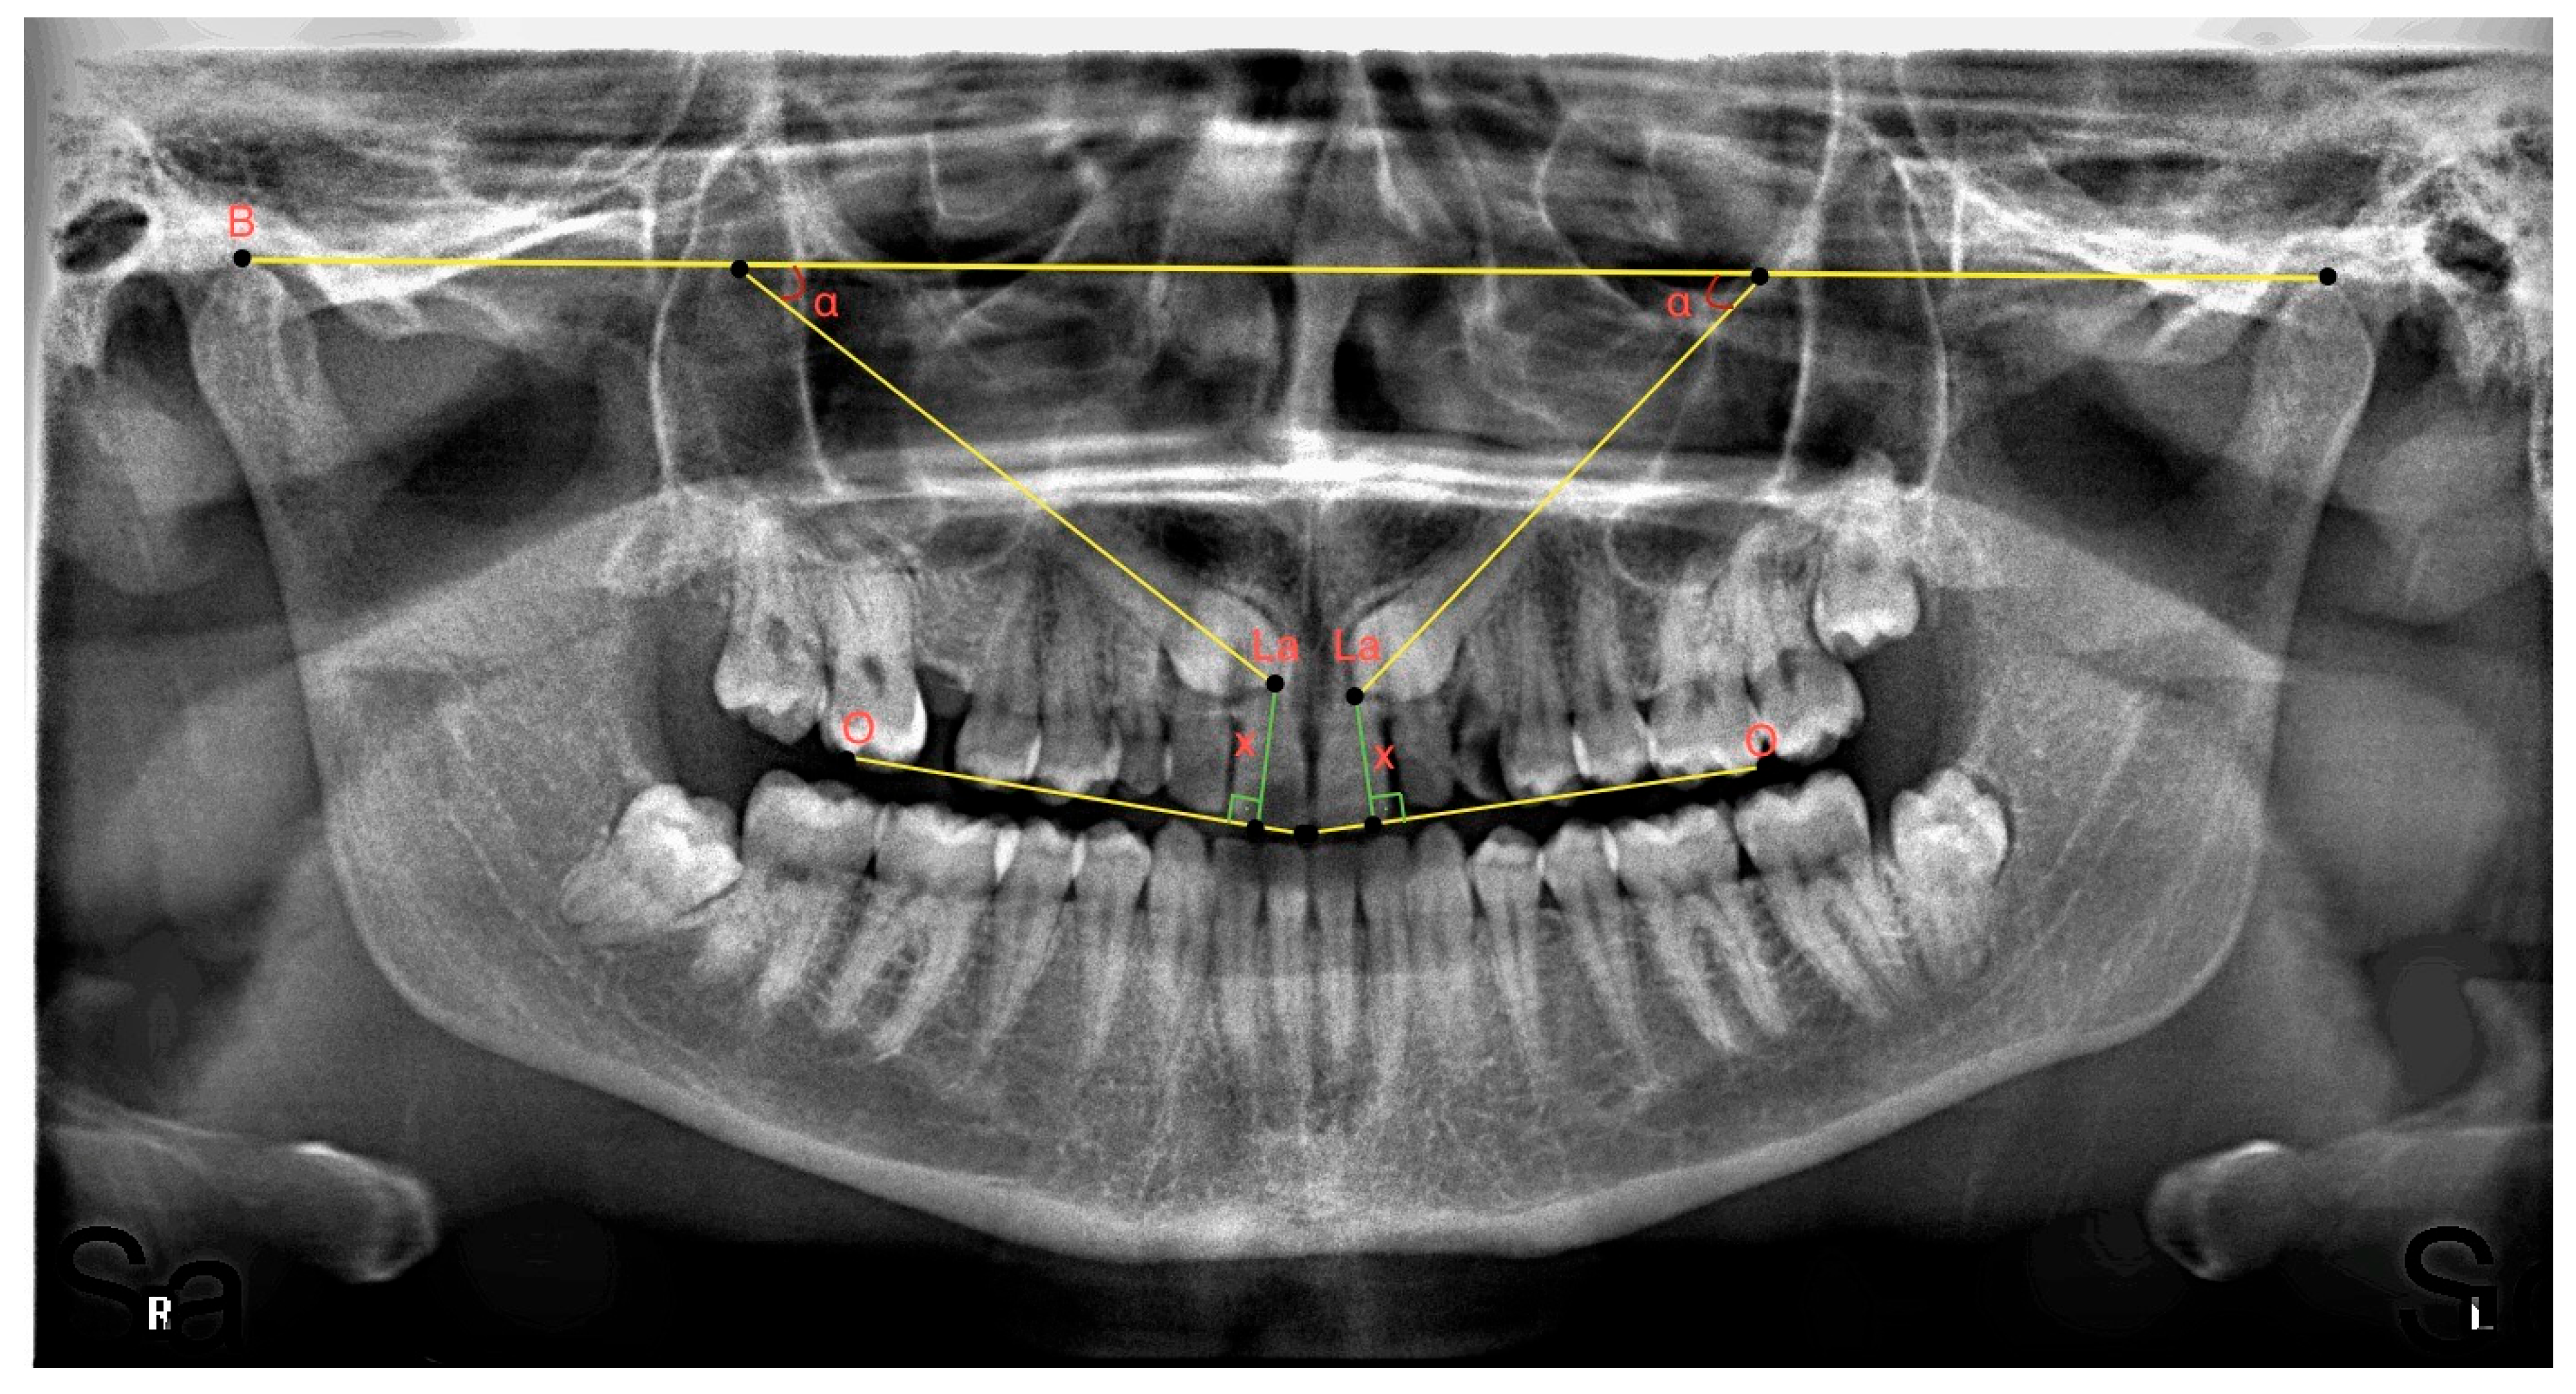

- As the relationship of the impacted maxillary canine to the adjacent lateral tooth increases (going from sector 1 to 4), the angle decreases, the distance to the occlusal plane increases, the tooth transitions to a more horizontal impacted position, and the probability of the tooth remaining impacted increases.